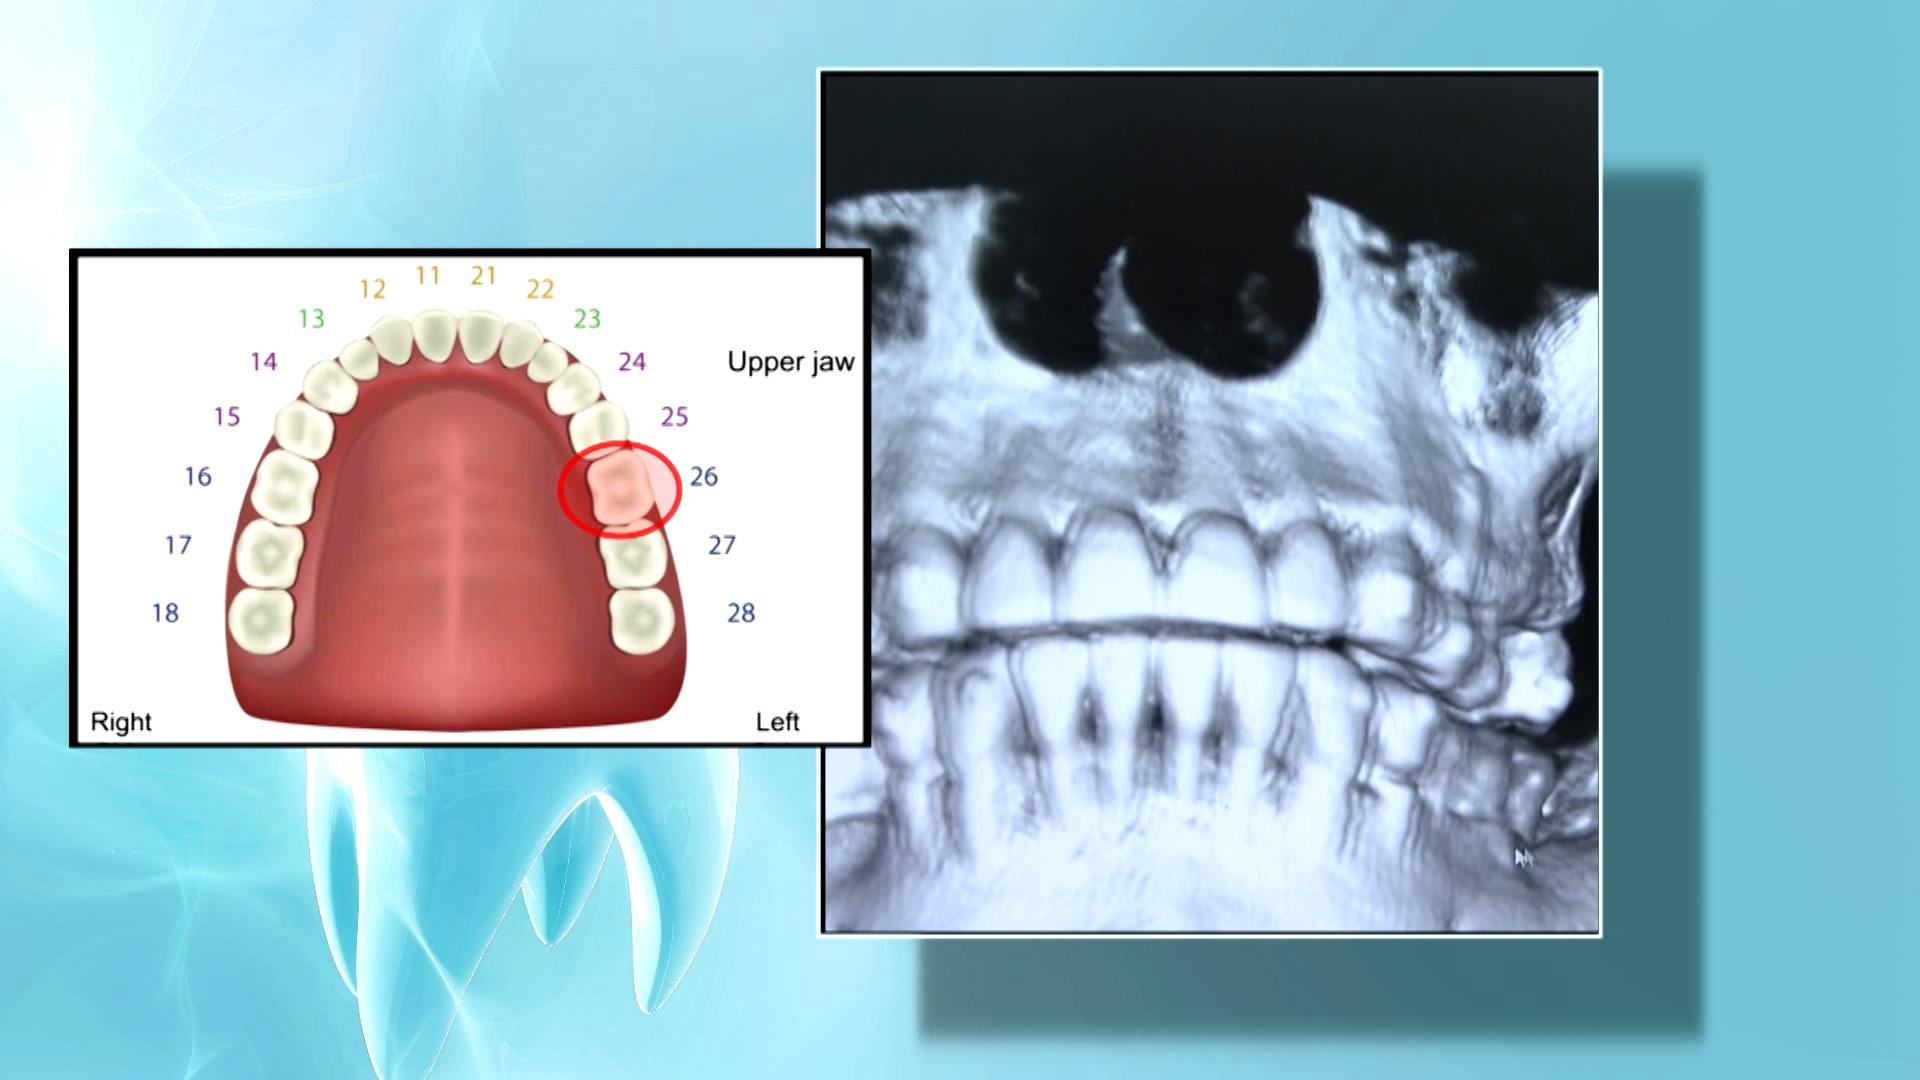

這宗橫跨五年的牙科事故,由2020年葉女士去觀塘一間診所求醫開始。當日由一位陳醫生,幫她拔除上顎的這隻大牙!不料。葉女士事後時不時感到拔牙位置痛楚,鼻塞呼吸不順。她自己也不明原因。

情況維持了三年。葉女士一直以為係自己「熱氣」所至!直到2023年8月,她北上內地種牙。一照X光,竟然發現令她痛足三年的原因︰拔牙位置殘留了牙腳!

2025 12月6日,由於在內地箍牙的緣故,葉女士不時要北上覆診,內地牙醫見她說不舒服,就幫她檢查,結果一查之下,X光片顯示拔牙位發炎,牙骨很薄,或因鼻咽膜穿孔,導致鼻孔流出黃色液體。

東張陪同葉女士去見一位牙科專家,經過幾個小時檢查,牙科醫生陳澔賢指, 事主鼻竇炎很可能是由殘留牙腳引起。